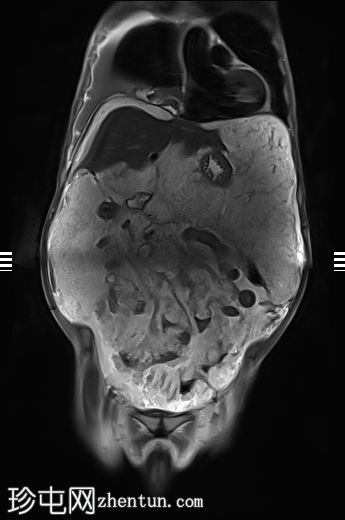

轴向

T1

升结肠壁增厚,尤其前壁,形成肿块,T2信号高,提示其为黏液性肿块。肿块无扩散受限,增强扫描后几乎无强化。

腹腔内可见大量T2信号高、T1信号低至中等的包裹性积液,与腹膜凹陷相符,并导致内脏表面(尤其是肝脏和脾脏)呈扇贝状。这些表现是腹膜假黏液瘤的特征性表现,可能由黏液性肿瘤播散引起。

在MRI上区分粘液腺癌和普通结肠腺癌的最佳方法是:粘液型腺癌显示高T2信号,无弥散受限;而普通型腺癌显示中至低T2信号,并伴弥散受限。